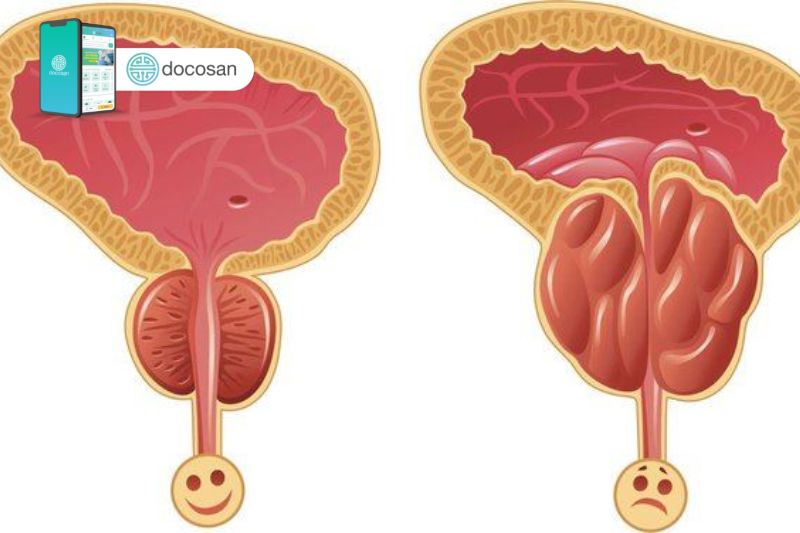

Tuyến tiền liệt là cơ quan sinh dục nam nằm ở phía dưới bàng quang và bao xung quanh niệu đạo có chức năng sản xuất tinh dịch. Khi đàn ông càng lớn tuổi, tổ chức mô tuyến này sẽ có xu hướng phát triển tăng kích thước và gây chèn ép đến đường dẫn nước tiểu của niệu đạo.

Từ đó kích thước phì đại tiền liệt tuyến sẽ có ảnh hưởng đến sức khỏe sinh sản và sinh hoạt của bệnh nhân nam. Để xác định một nam giới có kích thước phì đại tiền liệt tuyến hay không thì phải xác định được kích thước tuyến tiền liệt bình thường chuẩn theo từng giai đoạn.

Qua các giai đoạn bệnh tiến triển thì kích thước phì đại tiền liệt tuyến sẽ to dần và gây ra các biến chứng chèn ép cụ thể hơn.

Kích thước phì đại tiền liệt tuyến giai đoạn 1

Giai đoạn này thì tuyến tiền liệt chưa bị tổn thương đến mô, nhưng do kích thước phì đại tiền liệt tuyến bắt đầu tăng lên kèm với khối u xuất hiện ở thùy giữa có thể gây chèn ép lên bàng quang khiến bàng quang bị kích thích. Từ đó dẫn đến các triệu chứng của u xơ phì đại tuyến tiền liệt như buồn tiểu, đi tiểu nhiều cả ngày lẫn đêm, tiểu khó, tiểu buốt.

Kích thước phì đại tiền liệt tuyến giai đoạn 2

Lúc này sẽ bắt đầu xuất hiện những tổn thương thực thể của tuyến, biểu hiện qua các triệu chứng phì đại tuyến tiền liệt rất đặc trưng như: bàng quang giãn rộng, nước tiểu ứ đọng, tiểu gắt buốt, tiểu nhiều lần không hết, cường độ tắc nghẽn ngày càng tăng lên, ảnh hưởng tới chất lượng cuộc sống và chức năng sinh sản.